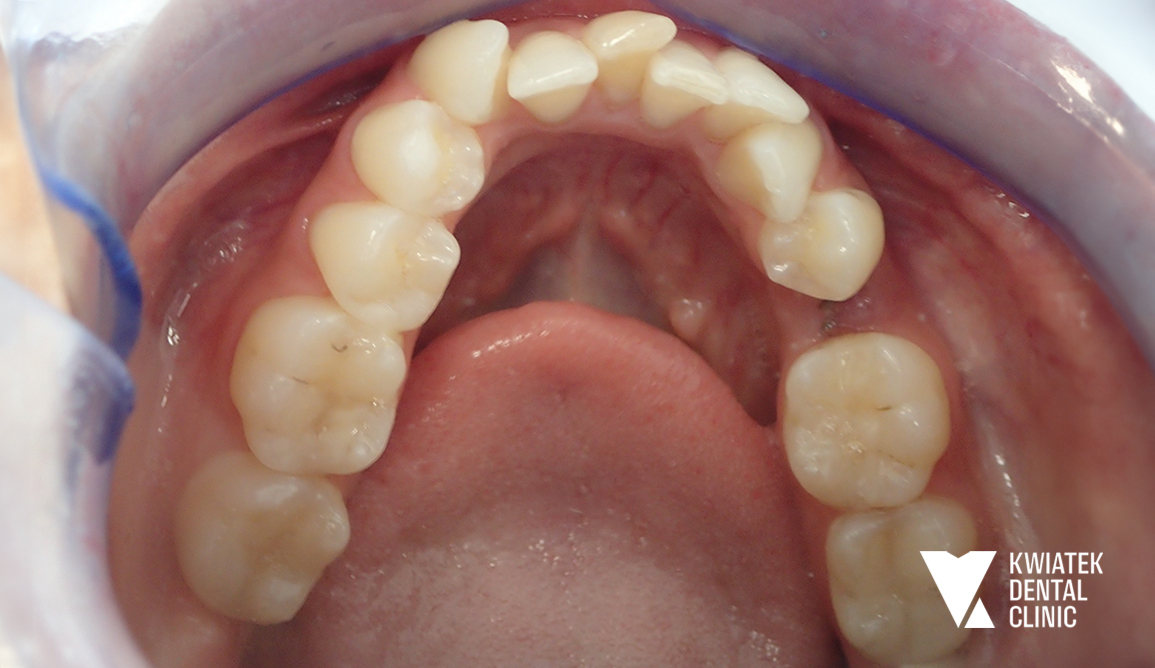

PRZED

Historia tej metamorfozy pokazuje, jak ogromne znaczenie ma kompleksowe podejście do leczenia stomatologicznego. Pacjentka zgłosiła się z chęcią poprawy estetyki uśmiechu, jednak już pierwsza konsultacja ujawniła, że kluczem do osiągnięcia trwałego efektu będzie nie tylko estetyka, ale przede wszystkim przywrócenie zdrowia i prawidłowej funkcji całego układu stomatognatycznego. To właśnie takie przypadki wymagają indywidualnego planu leczenia, cierpliwości oraz ścisłej współpracy Pacjentki z zespołem specjalistów.

Szczegółowa diagnostyka, obejmująca badanie kliniczne oraz zdjęcie panoramiczne, wykazała rozległe potrzeby lecznicze. Zidentyfikowano:

• wyraźne stłoczenia zębów, szczególnie w łuku dolnym

Diagnostyka ortodontyczna potwierdziła dodatkowo przesunięcie linii pośrodkowej oraz niewystarczającą przestrzeń w łukach zębowych, co wymagało precyzyjnego planowania leczenia.